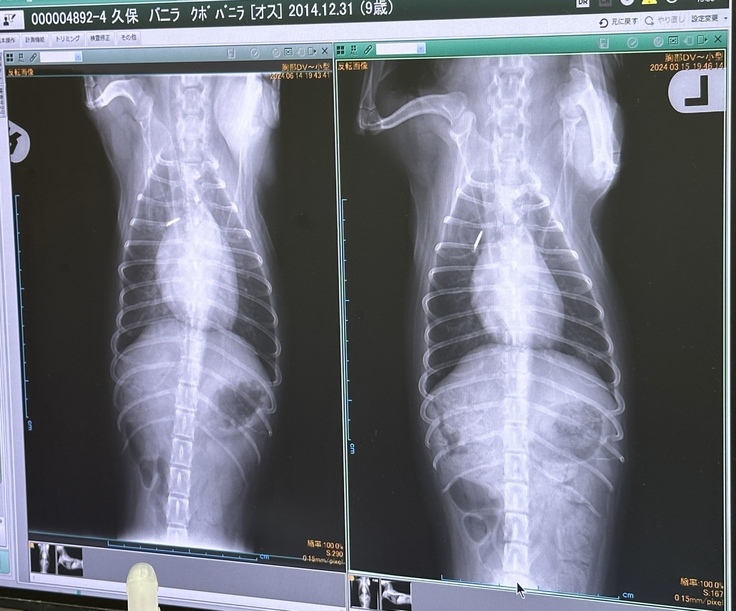

酸素室に少し入り、レントゲン・エコーの検査をしていただきました。

結果は、初期の肺水腫でした💦

心臓がやはり大きくなってきているので、

左が本日のX線。前より肥大してます。